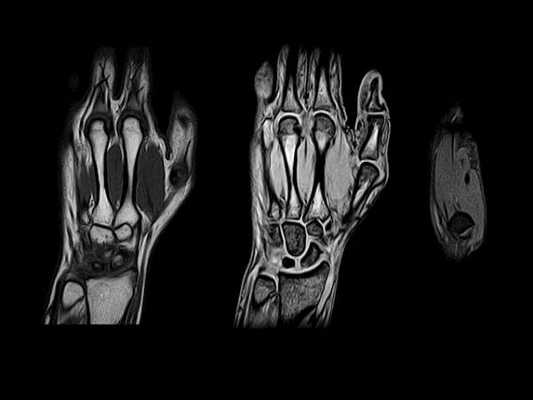

(Слева) МРТ, протон-взвешенное изображение, аксиальный срез: у пациента, ранее перенесшего операцию раскрытия запястного канала (РЗК) вследствие нейропатии срединного нерва, визуализируется эвентрация содержимого запястного канала через зияние в удерживателе сгибателей. Это характерный признак после РЗК.

(Справа) МРТ, протон-взвешенное изображение, аксиальный срез: у пациента после РЗК наблюдается обширный дефект удерживателя сгибателей. Данный дефект обычно выявляется около трапециевидной кости. (Слева) МРТ Т1ВИ, аксиальный срез: у пациента с нейропатией локтевого нерва и положительным симптомом Фалена определяется увеличение локтевого нерва на уровне гороховидной кости, что соответствует невриту локтевого нерва. Как и в большинстве случаев, внешняя компрессия не выявляется.

(Справа) МРТ Т2ВИ в режиме подавления сигнала от жира, аксиальный срез: у этого же пациента визуализируется умеренное усиление сигнала от локтевого нерва, что соответствует невриту. Сигнал от срединного нерва не изменен. В трехгранной кости обнаруживаются дегенеративные кисты. (Слева) МРТ протон-взвешенное изображение, аксиальный срез, пациент с нейропатией локтевого нерва и слабостью в руке: визуализируется однородное, среднеинтенсивное объемное образование овоидной формы, что соответствует ганглиону, который располагается с ладонно-локтевой стороны и вызывает смещение локтевого нерва проксимальнее канала Гийона.

(Справа) МРТ Т1ВИ, коронарный срез: у этого же пациента проксимальнее гороховидной кости наблюдается ганглион, вызвавший смещение локтевого нерва в проксимальную сторону (отмечено указателями). После резекции кисты симптомы исчезли.